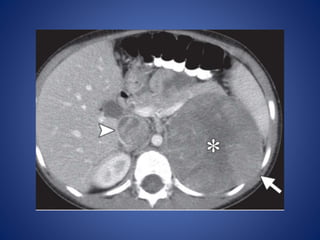

At CT, large ACNs show heterogeneous, predominantly peripheral

enhancement.

The tumor may be surrounded by a thick, capsule-like rim that

enhances. Fine or coarse calcification is seen at CT in about 30% of

cases

• #40 Adrenal cortical carcinoma in a 5-year-old girl. Post-contrast: large left retroperitoneal mass (arrow) with central necrosis (*). Tumor thrombus (arrowhead) is seen in the inferior vena cava